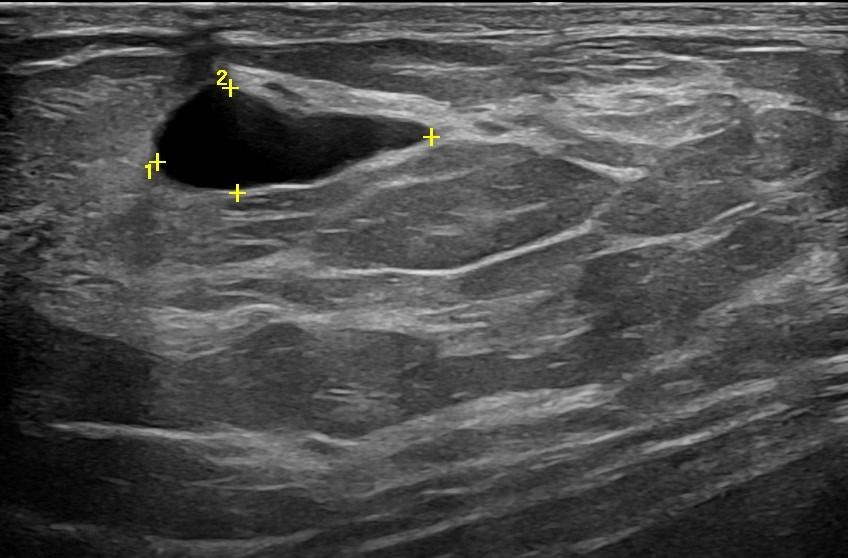

Modern ultrasound machines, equipped with advanced high-frequency transducers, techniques such as Color Doppler, Power Doppler, B-Flow, and Elastography, allow the analysis of breast architecture with exceptional accuracy.

Elastography can highlight the elasticity of a lesion, indicating whether it is hard or soft. Through this technique, we can assess the nature of the lesion, providing indications of whether it is benign or malignant. Additionally, with the contribution of Color Power Doppler and B-Flow, we can monitor the vascular flow within the lesions, offering even more information about the type and nature of the abnormality.